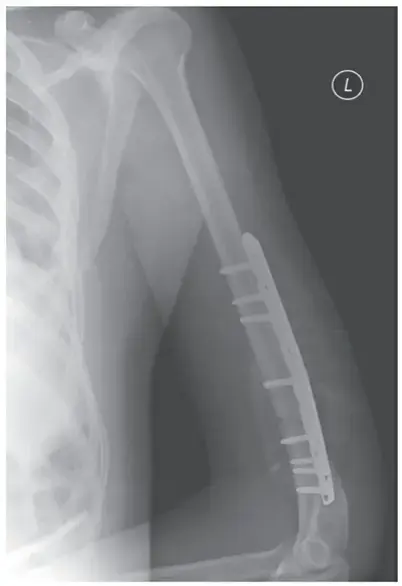

كسور عظم العضد القريب: دليل شامل للمرضى في اليمن والخليج العربي مع الأستاذ الدكتور محمد هطيف

كسور عظم العضد القريب هي إصابات شائعة بالكتف، غالبًا ما تنتج عن السقوط، وتصيب كبار السن بشكل خاص. معظمها يشفى بدون جراحة باستخدام الجبيرة والعلاج الطبيعي، بينما تتطلب الكسور المعقدة التدخل الجراحي لاستعادة وظيفة الذراع وتجنب المضاعفات، مع التركيز على التأهيل لاستعادة الحركة الكاملة.